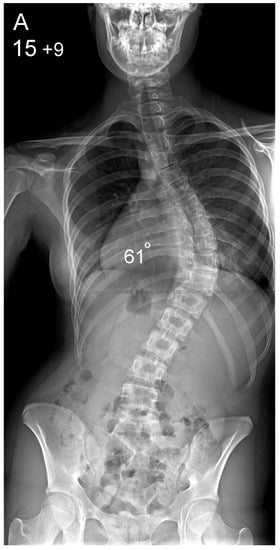

Figure 1.

Patient aged 15 years and 9 months with a right thoracic AIS producing thoracic translocation and listing of the trunk to the right, as well as thoracic flat back producing negative global sagittal balance of the spine and compensatory cervical kyphosis (A,B). The patient underwent posterior scoliosis correction using the AS technique which restored segmental and global coronal/sagittal spinal balance at latest follow-up (age 18 years and 8 months) into adult life (C,D). Clinical photographs demonstrate excellent correction of the coronal deformity and associated rib hump after scoliosis surgery (E–H).